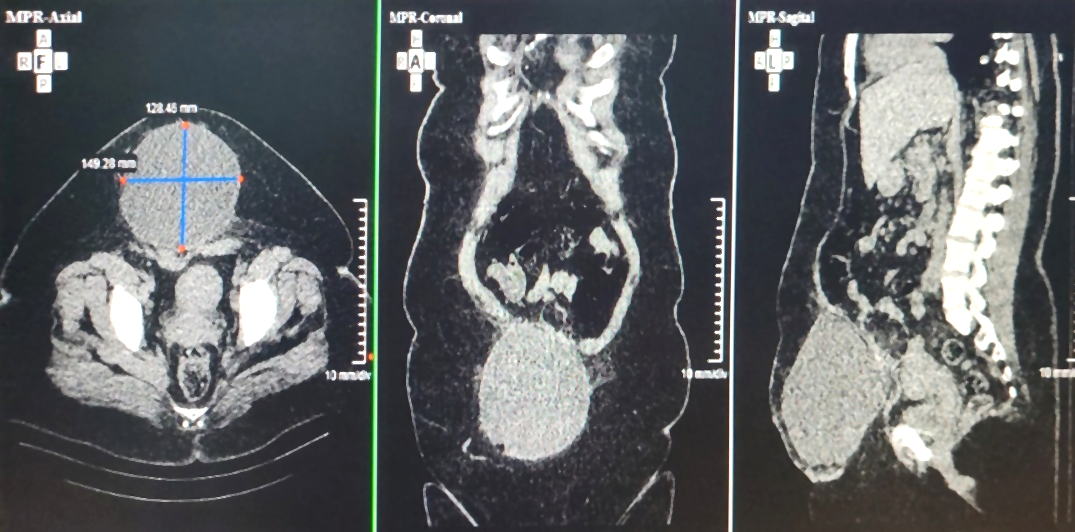

A los 2 meses de operada, regresó a consulta por aumento de volumen de la herida y dolor leve, además, del abandono ocasional de la compresión abdominal con faja. Al examen físico, se constata gran aumento del volumen de la herida quirúrgica, de aproximadamente 10 cm, de consistencia ligeramente renitente, con dolor leve a la palpación e irreductible. Se realizó tomografía computarizada (TC) del abdomen (Fig. 1 - Ver imagen con la resolución original) que informó imagen redondeada de 16 cm de diámetro, de contornos bien definidos, que se situaba en la pared abdominal anterior, en el sitio quirúrgico y que presentaba una densidad variable entre 3 y 20 UH.